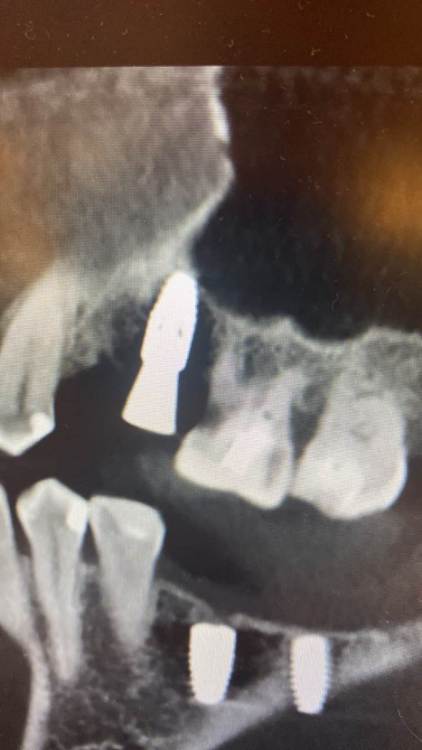

It'sGeorgy Опубликовано 3 февраля, 2022 Поделиться Опубликовано 3 февраля, 2022 (изменено) Коллеги, подскажите, с чем может быть связано такое настолько серьезное искажение на ОПТГ? 2 месяца думал, что завалил 1.5 в другую сторону, а на новом КТ оказалось все правильно. Скрытый текст Изменено 3 февраля, 2022 пользователем It'sGeorgy Ссылка на комментарий

kamranchick Опубликовано 3 февраля, 2022 Поделиться Опубликовано 3 февраля, 2022 лучше всего прицельник с позиционером, что оптг что кт не дают точной картинки, тем более штрауманн фонит будь здоров Ссылка на комментарий

It'sGeorgy Опубликовано 3 февраля, 2022 Поделиться Опубликовано 3 февраля, 2022 @kamranchick да, согласен, что лучше локсима + прицела после установки нет ничего. Но когда винтов много - просадка по времени получается, плюс асси с прицелом не всегда дружат. Но вышеуказанная ОПТГ дала повод задуматься целесообразности её в целом, если там настолько искажать может. 27 минут назад, kamranchick сказал: тем более штрауманн фонит будь здоров А разные винты с разной интенсивностью фонят? Не знал. Ссылка на комментарий